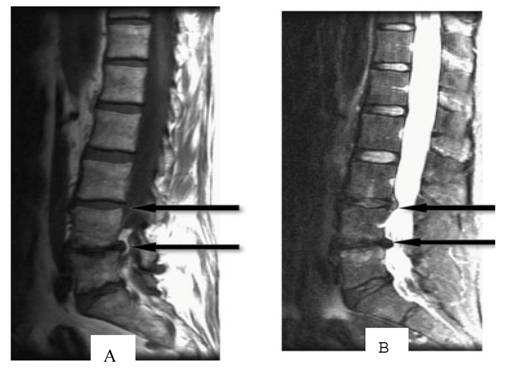

Low signal intensity of the disc on sagittal T2W

Age-related disc degeneration is associated with nucleus dehydration and matrix degradation, causing the T2W MRI signal intensity to decrease and resulting in a "black disc" (Figure 2). Studies have suggested that almost all discs showed reduced signal intensity upon sagittal T2W imaging in patients with varying degrees of disc degeneration and chronic LBP [18]. According to the extent of the reduced signal strength, Pfirrmann et al. [19] classified degeneration into five grades: I, which represents a normal disc, and II, III, IV and V, which respectively represent light to severe degeneration. However, many scholars believe that the parameter of low-signal intensity does not reflect a clear change in disc morphology and is only minimally associated with the amount of pain caused by DLBP [20-22]. In addition, in degenerative segments of lumbar vertebrae, it is not possible to distinguish which disc in the low signal intensity area has actually generated pain. In a study of healthy discs, Collins [20] found that 17% of discs had low signal intensity on T2W imaging. Therefore, low signal intensity of the disc has almost 100% sensitivity but a low specificity for DLBP; therefore, it is not suitable as a diagnostic tool.

Figure 2

T1 (A)- and T2 (B)-weighted MRI images of the spine show intervertebral disc signal intensity variations. Arrows point to pathological features (Adopted from Majumdar [18]).